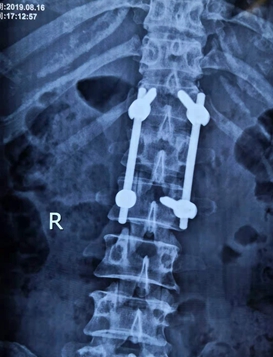

经过前期的充分探讨和准备,该手术在脊柱科主任李伟雄的带领下,术中C臂机透视定位腰1椎体及胸12、腰2椎体双侧椎弓根在体表投影并标记,胸12椎体及腰2椎体分别经皮闭合置入两枚椎弓根螺钉,经撑开固定后透视,骨折复位满意,螺钉位置及方向良好,椎体高度恢复满意。整个手术用时40分钟,术中出血仅20 ml,手术非常顺利。术后第二天,患者疼痛明显缓解,一周后在腰椎支架的保护下下床活动。

据娄底市骨伤医院脊柱科主任、副主任医师李伟雄介绍,胸腰椎椎体压缩性骨折经皮椎弓根螺钉内固定术,因其具有手术切口小,出血少,术后患者恢复快,住院时间短等优点,是近年来发展起来的一项新技术,也是目前微创治疗腰椎滑脱、胸腰椎骨折、椎管狭窄、肿瘤等脊柱疾病的一种先进手术方式。术中对脊柱周边肌肉组织干扰少,不需要大量剥离椎旁肌肉,创伤大大降低;恢复快,后遗症少,术后腰背痛和腰部乏力的机会大大降低。相比传统的大切口开放手术,极大地减少了疾病、创伤给患者给来的不便和痛苦,同时也为患者节约了住院成本,减轻患者经济负担。